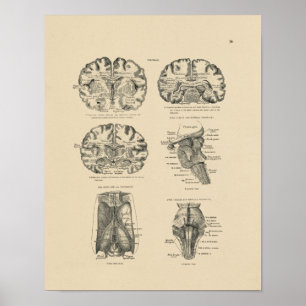

Impressão da anatomia 1880 do cérebro humano do

Preço23,90 €